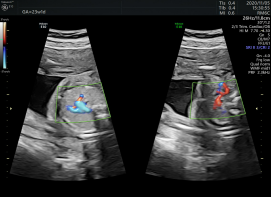

胼胝体周动脉超低速血流灌注状态

其他彩超机